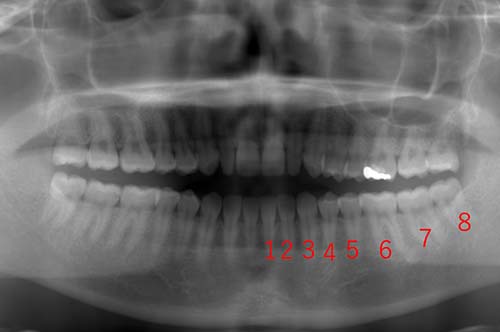

通常は17~22歳頃に出てきますが、まれに30~40歳頃に出てくることもあります。最近では、第三大臼歯は退化する傾向にある為、生えてこない人も増えています。親知らずは、ブラッシングをしても磨き残しが発生したり、まっすぐに生えていない為、歯肉に負担をかけたりするために、虫歯や歯肉炎になってしまう場合があります。写真では、歯に番号が振ってあり、前歯1番から数えて8番目が親知らずになります。このレントゲン写真では、親知らずが卵の状態でまだ抜くに至らない状態です。年齢は、16歳になります。この親知らずが卵の状態では、まだ抜歯するには時期早々になります。